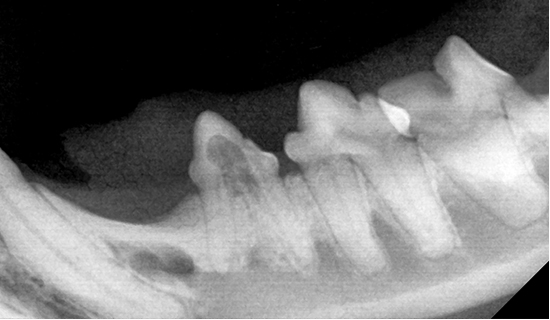

치아흡수병변 TYPE 및 예시

TYPE 1

TYPE 2

TYPE 3

치아흡수병변의 모습과 치아엑스레이 영상(Type1)

치아흡수병변의 모습과 치아엑스레이 영상(Type2)

치아흡수병변의 모습과 치아엑스레이 영상(Type3)